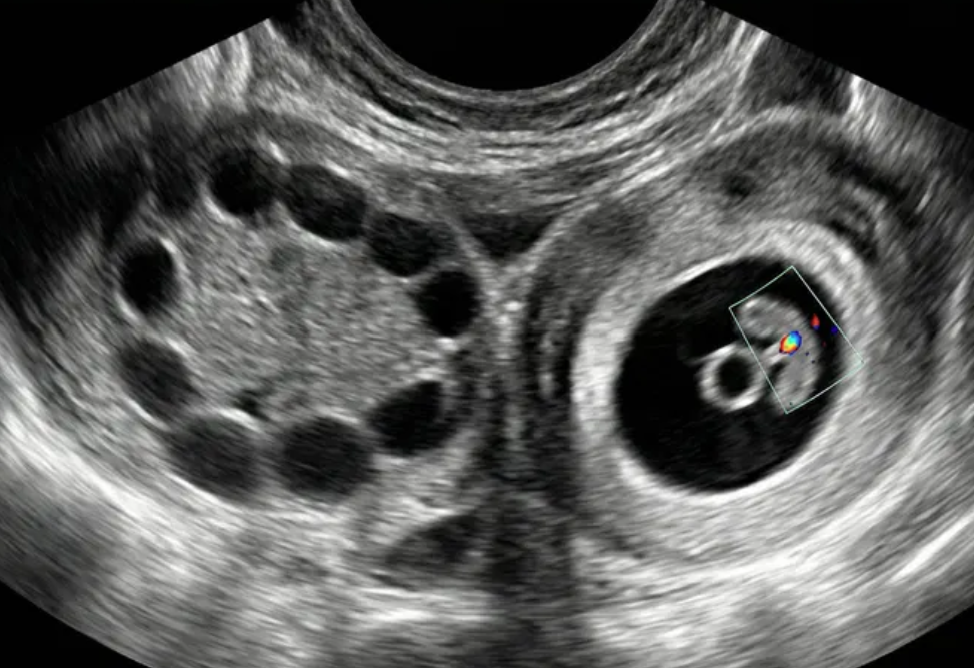

Gestação ectópica (US)

Ferramenta educacional baseada no NICE guideline NG126 (2019, atualização 2023), com abordagem conservadora. Ajuda a reconhecer sinais ultrassonográficos de gestação ectópica tubária e a lembrar a necessidade de correlação clínica e laboratorial.

Indica ectópica tubária (USTV)

Alta probabilidade (USTV)

Possível ectópica (USTV)